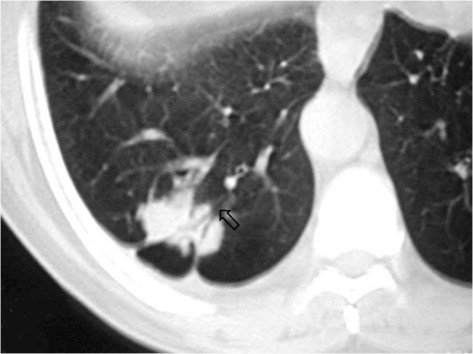

SIGNO DEL BRONQUIO ABIERTO O BRONQUIO POSITIVObronqposHallazgo visible en la TC de tórax que consiste en una imagen de hipodensidad tubular (el bronquio) que alcanza directamente un nódulo pulmonar periférico, en el que puede adentrar  (creándose un signo de broncograma aéreo) o no. En la imagen vemos el bronquio positivo –flecha- y el broncograma aéreo en el interior del nódulo.

Este signo no es específico de malignidad, ya que también está presente en lesiones benignas, como tuberculomas, masas inflamatorias o infartos. Más bien, la utilidad del signo reside en que, cuando está presente, la biopsia transbronquial está indicada y será muy probablemente rentable. Por el contrario, cuando no está presente, la biopsia transparietal es el mejor método para la confirmación histológica.